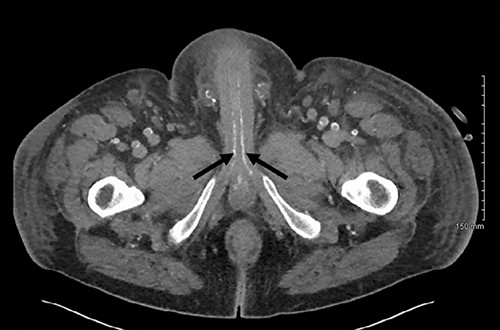

Axial slice of a non-contrast CT AP with arrows delineating calcified cavernosal arteries.

Post-operatively the patient was experiencing ongoing severe penile, examination of the glans was not possible due to oedema and pain. Our patient underwent dialysis to offload excess fluid. A CT angiogram revealed extensive peripheral vascular arterial calcification, including calcification of the internal pudendal and cavernosal arteries (Figs 2 and 3). The inguinal lymphadenopathy was shown to be reactive.

The gold standard for the diagnosis remains skin biopsy. Biopsy of the foreskin at the time of dorsal slit did not elucidate any calciphylaxis, however did out rule malignancy. Glansectomy and circumcision confirmed calciphylaxis with vessel calcification and necrosis. However, often times diagnosis is made based on presentation, bloods and imaging, due to the risk of biopsy potentiating infection. Radiological investigations can aid diagnosis. CT is the most sensitive, assessing the extent of vascular calcification, as in our case [1] (Figs 2 and 3).